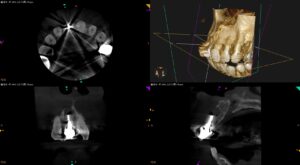

紹介患者さんの治療。 主訴は、 上の前歯の被せ物の歯茎が腫れて痛い… である。 歯内療法学的検査(2025.2.26) ☆この後、検査動画が出てきます。不快感を感じる方は視聴をSkipしてください。 患者さんは、 費用が … 続きを読む 上の前歯の被せ物の歯茎が腫れて痛い…〜#8 Apicoectomy